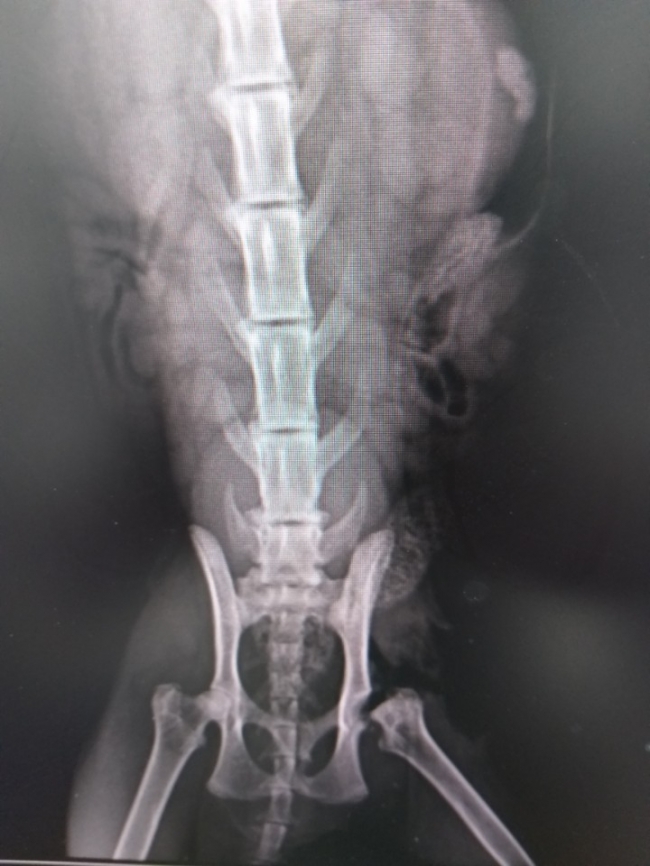

엑스레이상으로 왼쪽 뒷다리 대퇴골두가 나와있고 괴사된 것을 확인하였습니다. 마취된 아이의 왼쪽 뒷다리를 선생님이 움직여보자 소리가 날 정도였습니다. 혹시 학대가 아닐까 걱정했는데 학대는 아니고 선천적인 거라고 하셨습니다. 검사를 위해 마취한 김에 tnr을 하기로 하였습니다. 귀 컷팅은 혹시 몰라서 다리 수술 때 하기로 하였습니다.

아래 사진은 아이 수술 후 엑스레이 사진입니다. 왼쪽 대퇴골두 부분이 안으로 들어가 있습니다.